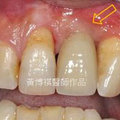

術後完成照 瀏覽31 推薦0

After 瀏覽28 推薦0